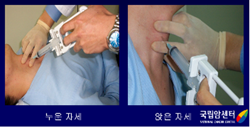

갑상선암의 미세침흡인세포검사(2)

2009.08.20

갑상선암의 미세침흡인세포검사(1)

2009.08.20